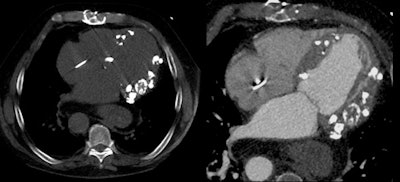

A case of restrictive cardiomyopathy showed extensive calcifications in the myocardium, which occurs fairly commonly and due to a range of causes, Becker said, noting a 2014 paper by Nance et al that clearly categorized the various differential diagnoses for findings of calcifications in the myocardium. One is dystrophic myocardial calcification caused by tissue damage due to ischemia, trauma, inflammation, or infection, or by tumor disease infiltration.

For example, a patient with end-stage renal disease had secondary hyperparathyroidism due to lack of compliance with medication or dietary restrictions; radiography showed extensive calcifications in the bones of the hand, with corresponding changes visible in the heart where extensive calcifications in the myocardium were associated with extensive pericardial effusion.

In a recent case from Stanford, myocardial calcifications were an incidental finding in a patient scheduled for aortic valve replacement.

"Unfortunately, I cannot provide a final diagnosis as to why the patient has so much calcium in the myocardium, but know it is certainly not secondary hyperparathoroidism because the creatinine was normal," Becker said. "My assumption is that this is of infectious origin."